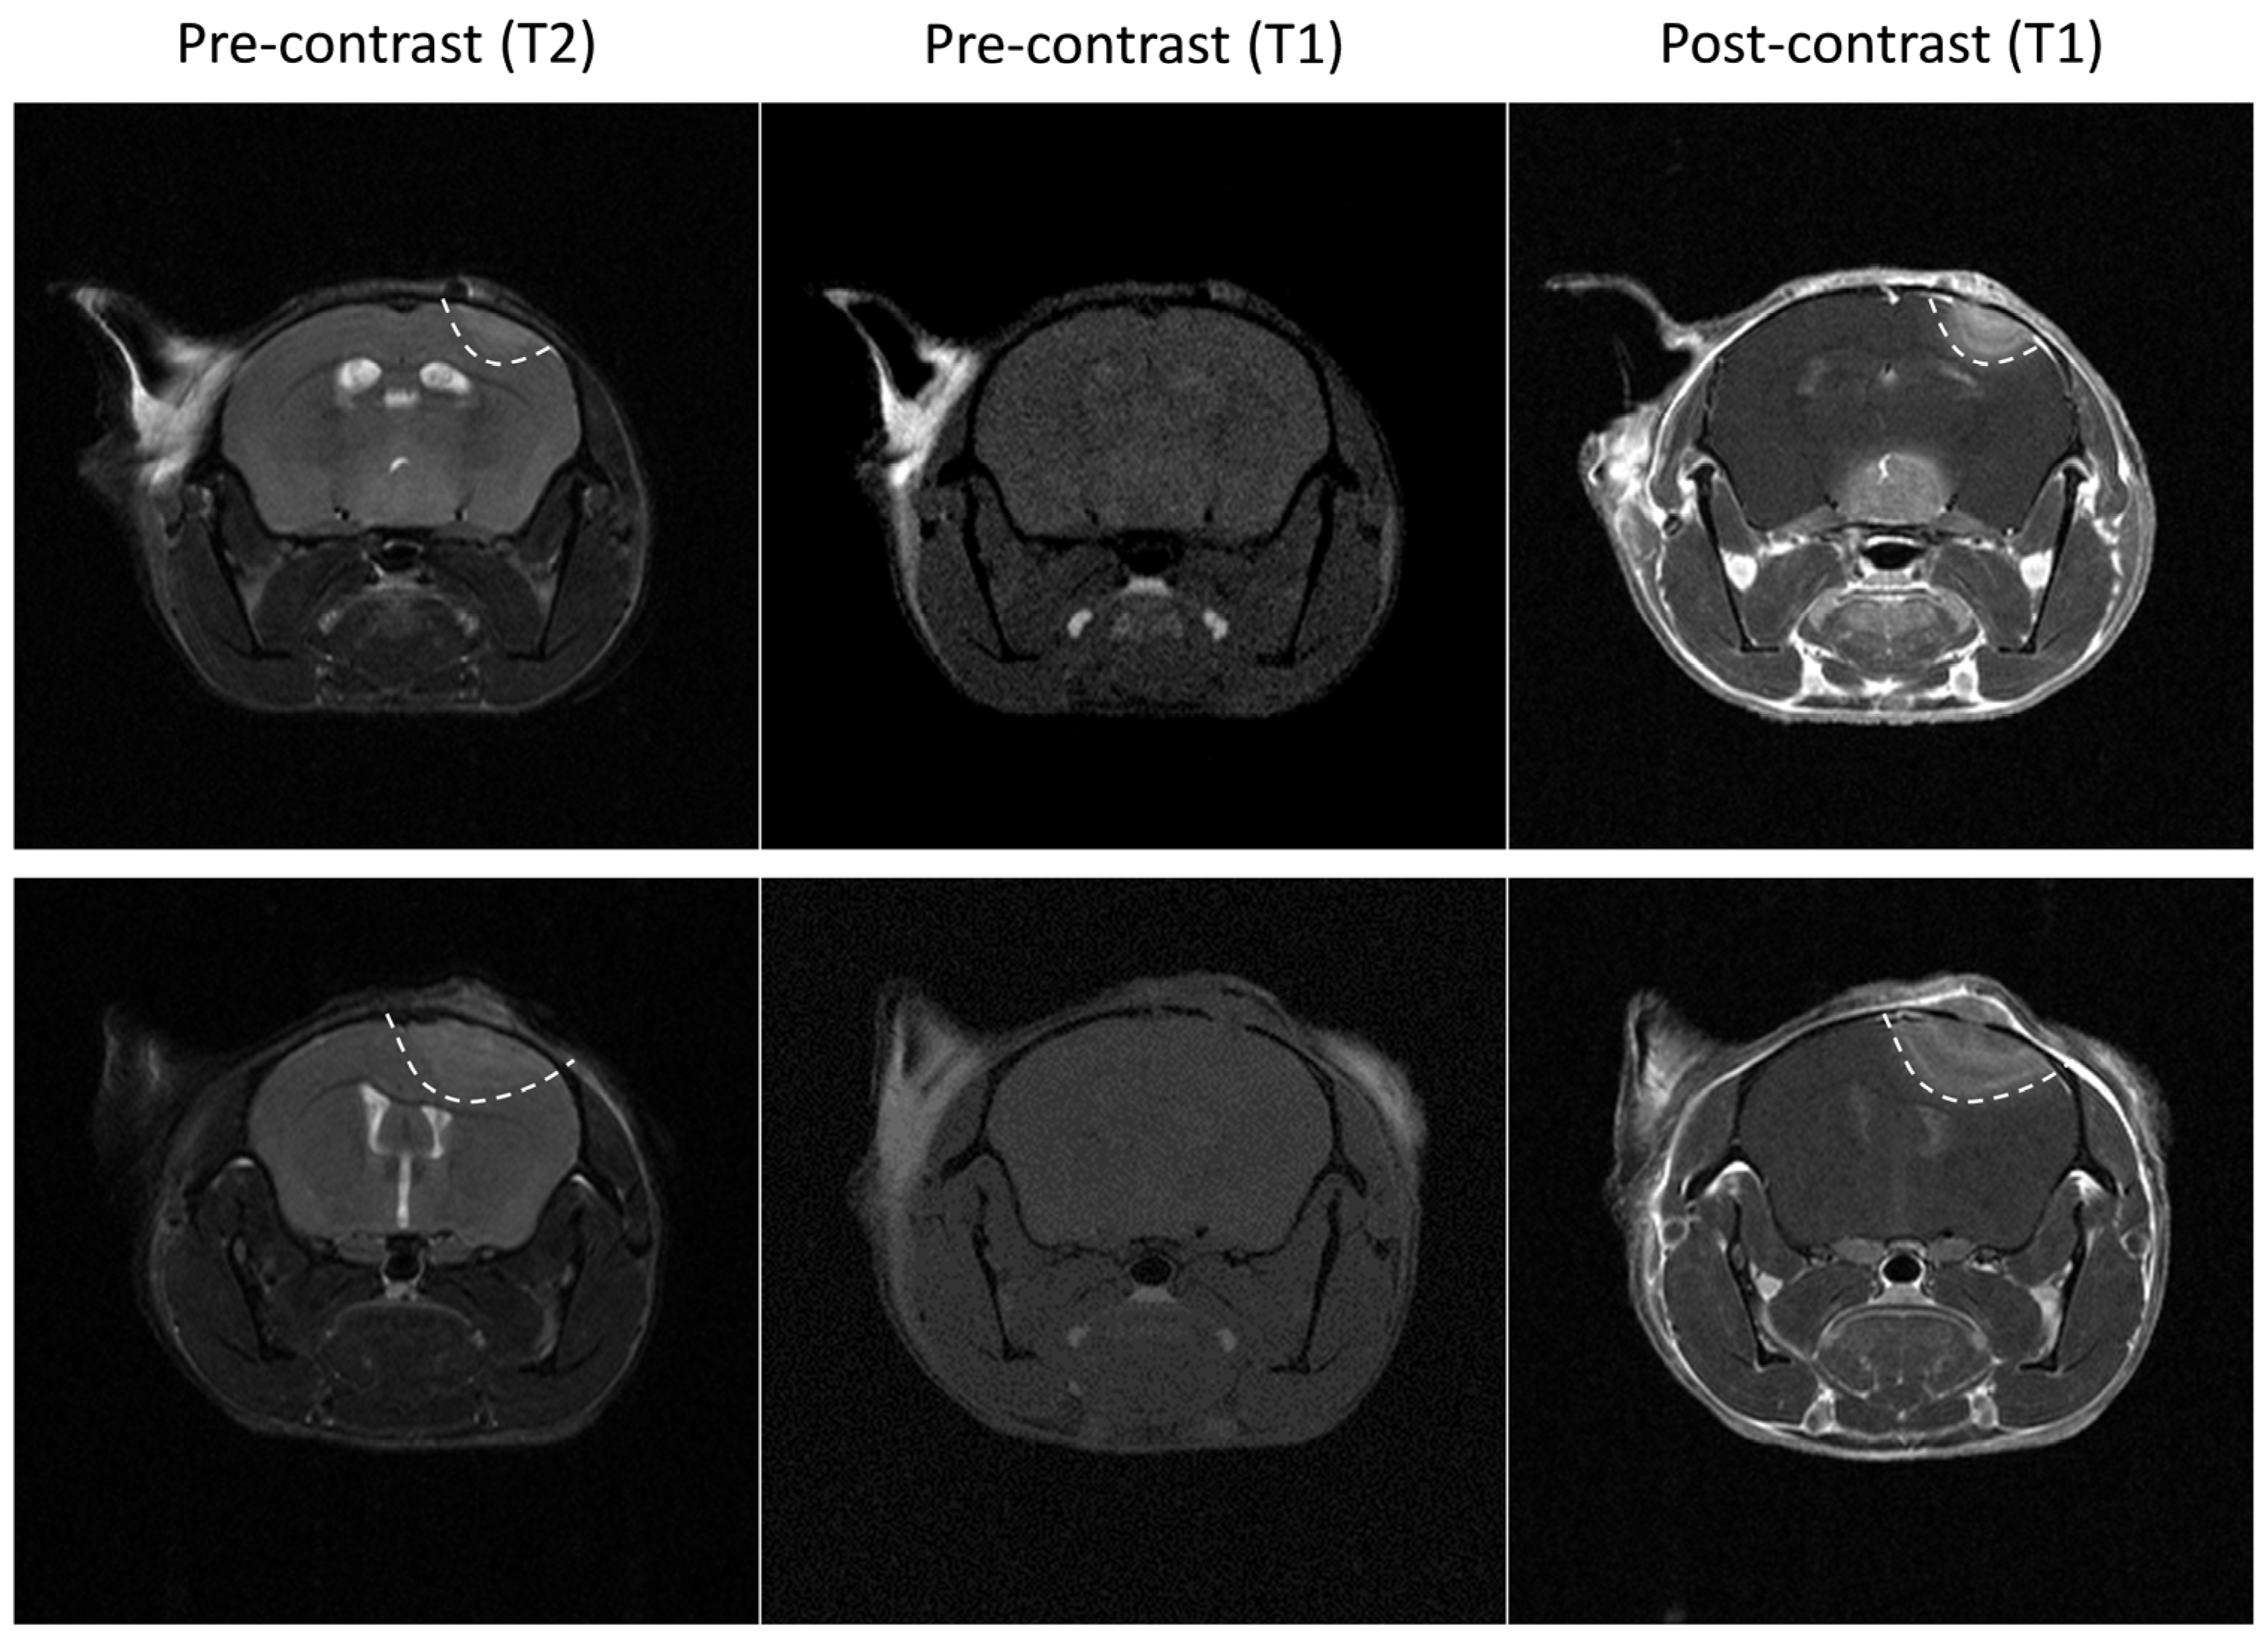

2.3. Tumor Imaging

2.3.1. Bioluminescence Imaging

2.3.2. Magnetic Resonance Imaging